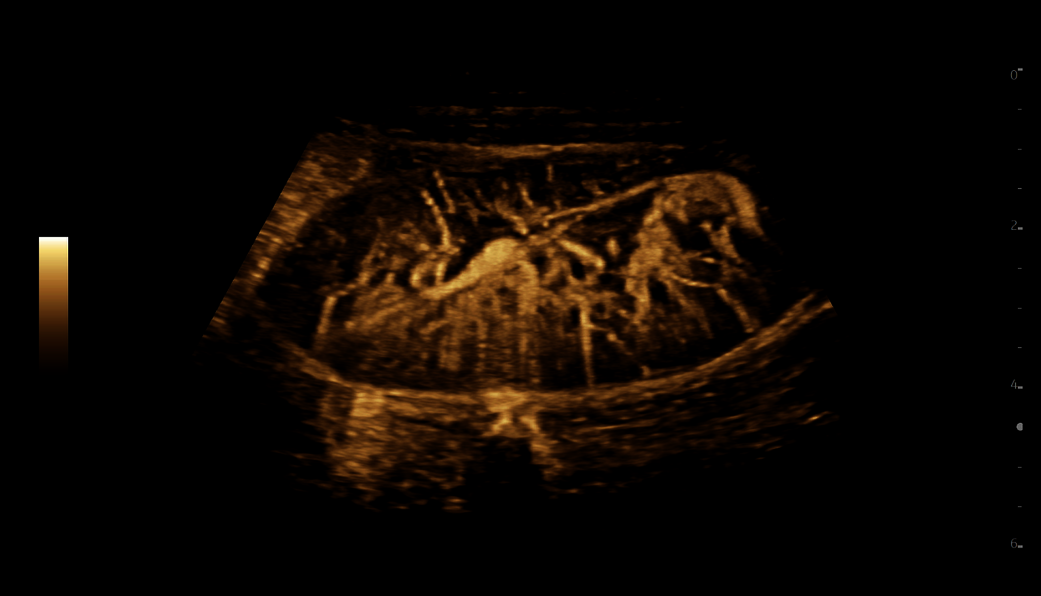

In pediatric ultrasound, the diversity of the caseload can be challenging. Clinicians need a non-ionizing radiation technology that can image a wide range of patients, from newborns to young adults, and acquire detailed information accurately and efficiently.

LOGIQ Ultrasound is your trusted companion. Designed for pediatric care, for every age and body type, across the full spectrum of childhood.

Accurate image quality and non-invasive imaging tools help you deliver fast, confident diagnoses across a wide range of patientsʼ conditions, from neonate cranial scans to abdominal or pelvic pain.

LOGIQ Ultrasound, with cSound™ Imageformer, enables delivering images of incredible uniformity from near to far field. Thereʼs no need to manually adjust the focus - the information you need is there, instantly.